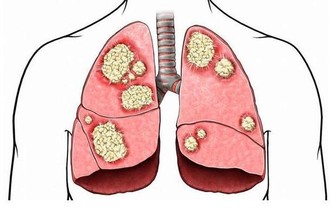

三、肺臟排毒

肺是最容易積存毒素的器官之一。因為人每天的呼吸會將約1000升空氣送入肺中,空氣中飄浮的許多細菌、病毒、粉塵等有害物質也隨之進入肺臟。當然,肺也能通過呼氣排出體內代謝的二氧化碳等廢氣和其他有害入侵者。

肺臟有毒素堆積,會使人經常感冒、咳嗽、哮喘,氣管敏感。中醫認為,肺臟和大腸是一套系統,互為表里。當肺臟有毒素時,腸道內也會有不正常淤積,出現便秘。